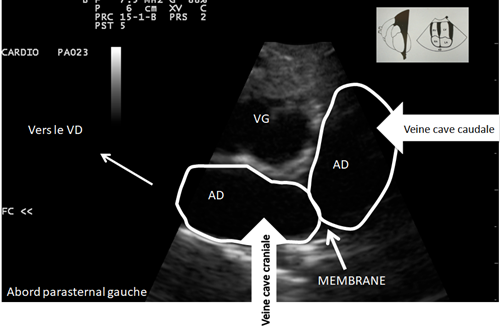

On a une sensation de bombement a certains endroits de l’AD

Bilan échocardiographique

- Confirmation de l’hypothèse de

Cor triatriatum dexter